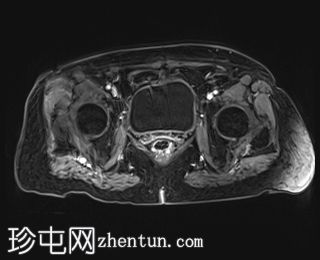

轴位

DWI

中下段直肠肿块,形态不规则,边缘清晰,质地不均一,以囊性为主,多分叶,增强扫描时实性部分强化,弥散不受限,病灶下缘位于肛门直肠连接处30毫米处,呈半圆形,横跨半径3点至9点方向,纵轴长约44毫米,向直肠系膜脂肪方向延伸达15毫米,但未超过直肠系膜筋膜。直肠上段无改变。未观察到淋巴结肿大。

此外,可见子宫呈前屈状,外观不均匀,内部信号低,呈卵圆形,边缘清晰,造影剂应用后出现不均匀强化,从而影响了子宫内膜的体积效应。子宫横、前后和头尾方向的尺寸分别为 2.9 x 2.8 x 4.0 cm,与黏膜下肌瘤相关。

病理报告证实为高分化 G1 肠腺癌。患者已接受放疗和化疗。肿瘤分类为 T3。